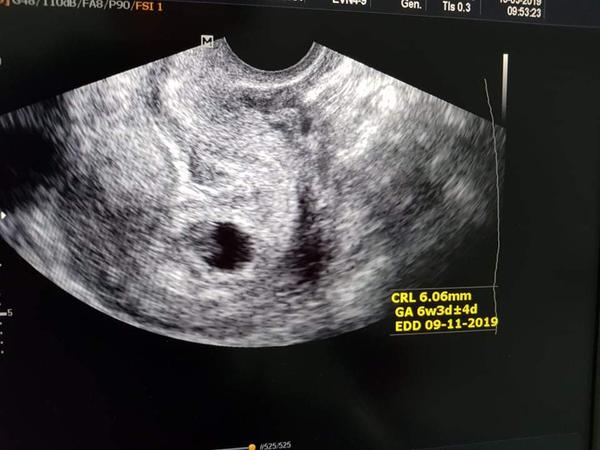

Ahojte baby. Neviem ci este niekto na mna spomina. Prispievala som hlavne na zaciatku. Vcera som bola na prvej kontrole ultrazvukom. Bola som 6+5 podla posledneho MS a 6+4 podla OPU. Bolo to carovne. Videli sme nasho drobceka a bilo sa mu srdiecko 😍. Manzel plakal od stastia a ja tiez 🙂. Vsetko je v poriadku, rozlucili sme sa v centre, dostala som prepustaciu spravu a na dalsiu kontrolu idem uz ku svojmu gyn. O 2 tyzdne este kontrola na hematologii, lebo pichala som (aj picham) Fraxiparine kvoli OHSS a teraz mi to uz boja zobrat bez vyjadrenia odbornika. Z celeho srdca Vam prajem, aby ste to zazili v co najkratsom case, idealne do par tyzdnov 😉. Kazda bolest, neprijemnostnost aj slza stala za to. Vydrzte to, oplati sa 😊 !

Este pripajam fotku nasho drobceka (svetlejsia fazulka v ciernom kruhu v strede fotky) 🙂 .